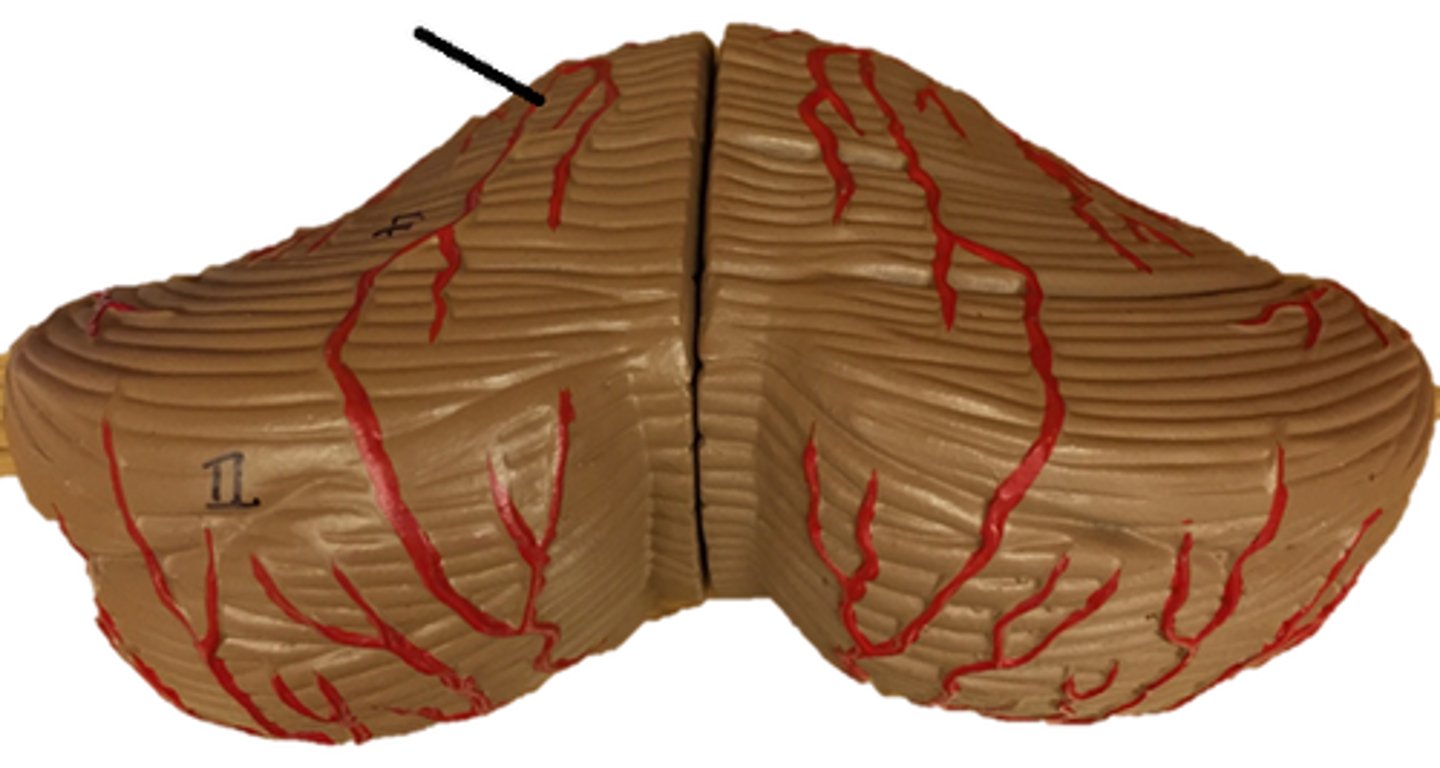

Cerebellum

anterior lobe of cerebellum

posterior lobe of cerebellum

vermis

folia

arbor vitae

Primary fissure